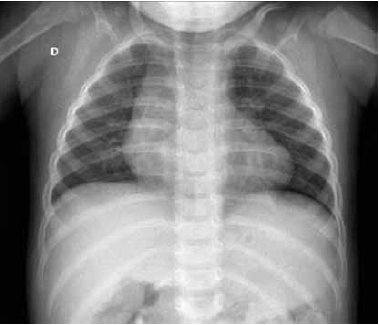

Criança de 2 anos e 3 meses, 13 kg, é admitida na Unidade de Terapia Intensiva com hipótese diagnóstica de crise asmática grave. No pronto-socorro, já havia recebido 3 ciclos de Salbutamol – 4 puffs, 6 puffs e 8 puffs – sem melhora, metilprednisolona 25 mg endovenoso e sulfato de magnésio – 650 mg em 30 minutos. Instalado cateter nasal de alto fluxo – 20 L/minuto com FiO2 50%, mas mantendo desconforto respiratório moderado a grave, frequência respiratória – 55, saturação de oxigênio – 93% e retração intercostal e subdiafragmática, além de batimento de asa de nariz. Antecedente pessoal – nunca teve crise de broncoespasmo anterior; antecedente familiar – pais saudáveis, negam asma, rinite ou alergias, irmã mais velha escolar saudável, mas teve gripe há 1 semana. Quando questionada sobre engasgos recentes, a mãe relata que, há cerca de 4 dias, teve uma crise de tosse enquanto comia arroz integral, sete cereais, mas não tem certeza se engasgou ou pegou a gripe da irmã. Depois disso, com tosse esporádica e hoje cansaço.

No pronto-socorro, foi realizado o seguinte Rx de torax.

Quais são a hipótese diagnóstica e a conduta neste caso?